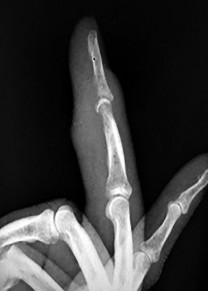

A 28-year-old carpenter sustains a sharp knife laceration to the volar aspect of his index finger at the level of the proximal phalanx. He is unable to flex the DIP and PIP joints. Which zone of flexor tendon injury does this represent, and what is its anatomic definition?

Zone II flexor tendon injuries occur between the distal palmar crease (the proximal edge of the A1 pulley) and the insertion of the flexor digitorum superficialis (FDS) on the middle phalanx. Historically termed 'no man\'s land' by Bunnell, this zone contains both the FDS and FDP tendons tightly enclosed within the flexor tendon sheath, making repair prone to adhesions.